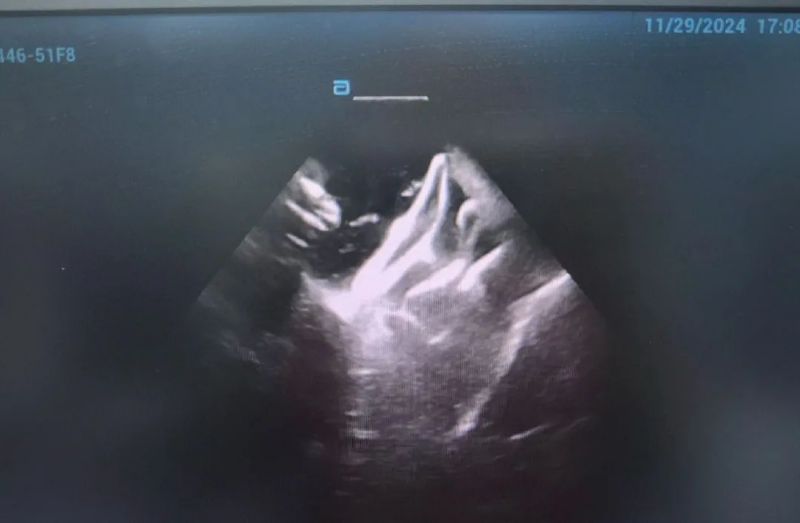

近日,延安大學(xué)咸陽醫(yī)院成功實(shí)施了咸陽地區(qū)首例脈沖場消融術(shù)、首例脈沖場消融+左心耳封堵“一站式”治療房顫手術(shù)2例手術(shù)的順利完成,標(biāo)志著我院在心律失常治療技術(shù)上的又一重大突破!

此次手術(shù)患者均為持續(xù)性房顫患者,由延安大學(xué)咸陽醫(yī)院吳棟梁院長、心律失常專家劉雄濤副院長帶領(lǐng)介入團(tuán)隊(duì)開展,安全高效、圓滿完成手術(shù),手術(shù)過程患者全程清醒,術(shù)中自訴感覺良好,無痛苦感受。術(shù)后患者的心律恢復(fù)并維持了竇律,目前恢復(fù)情況良好,無任何并發(fā)癥出現(xiàn)。